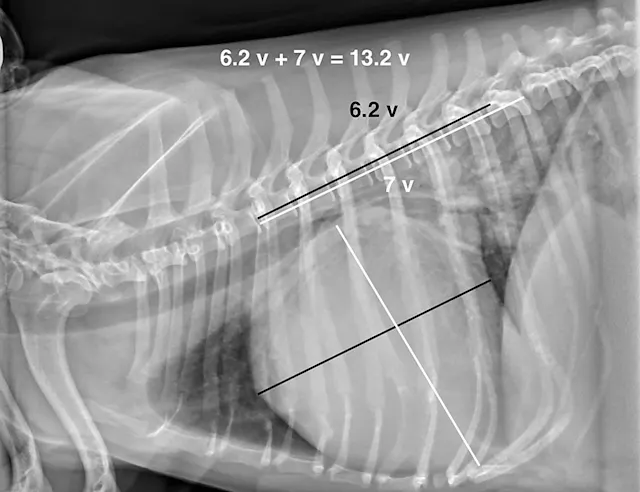

In dogs and cats, the vertebral heart score (VHS) system measures the width of the cardiac silhouette (ie, distance from cranial to caudal [ie, short axis] along the estimation of where the atria and ventricles meet) and from the carina of the trachea to the apex of the heart at its most ventral point (lines [ie, long axis] should be perpendicular to each other). These measurements are transferred caudally starting at T4 to calculate the VHS (Figure 4).2 Although this measurement is a good general guide, it can be overinterpreted, as cardiac chambers can change size without changing the shape of the cardiac silhouette.3

The average VHS in dogs is approximately 9.5 ± 0.5 with a normal range of 8.7 to 10.7. The measurement can change based on right or left recumbency (see a compilation of breed-specific VHS reference ranges available from Nguyenba in Suggested Reading). Measurements are more useful when diagnosing dilatative forms of cardiac disease and are reported to be less accurate in dogs with cardiac diseases with concentric hypertrophy.3 VHS for cats in right lateral recumbency is 7.3 ± 0.5.4 A VHS >7.9 has a high diagnostic accuracy in distinguishing cats with left-sided cardiac disorders from healthy cats.5